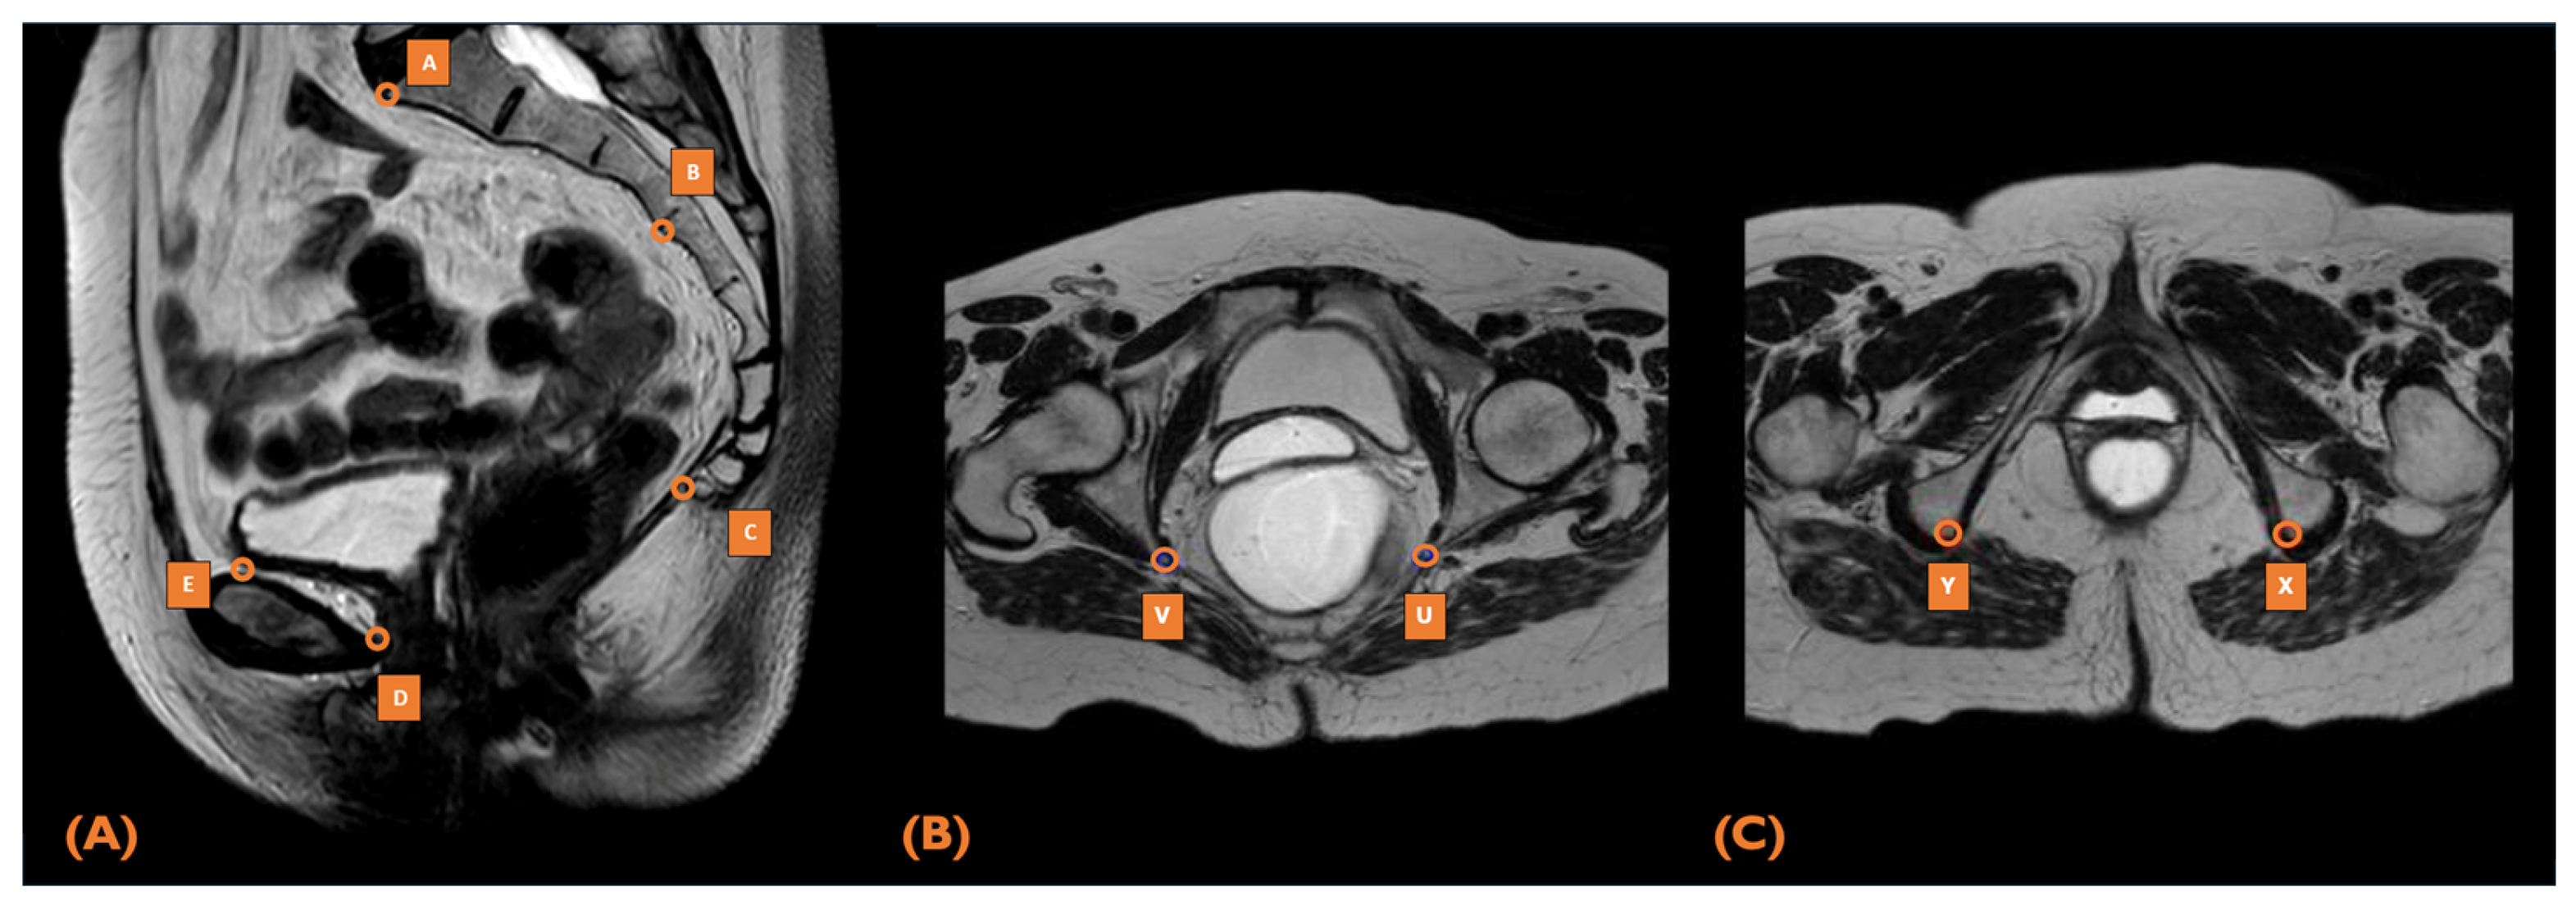

2.5. MRI Pelvimetry